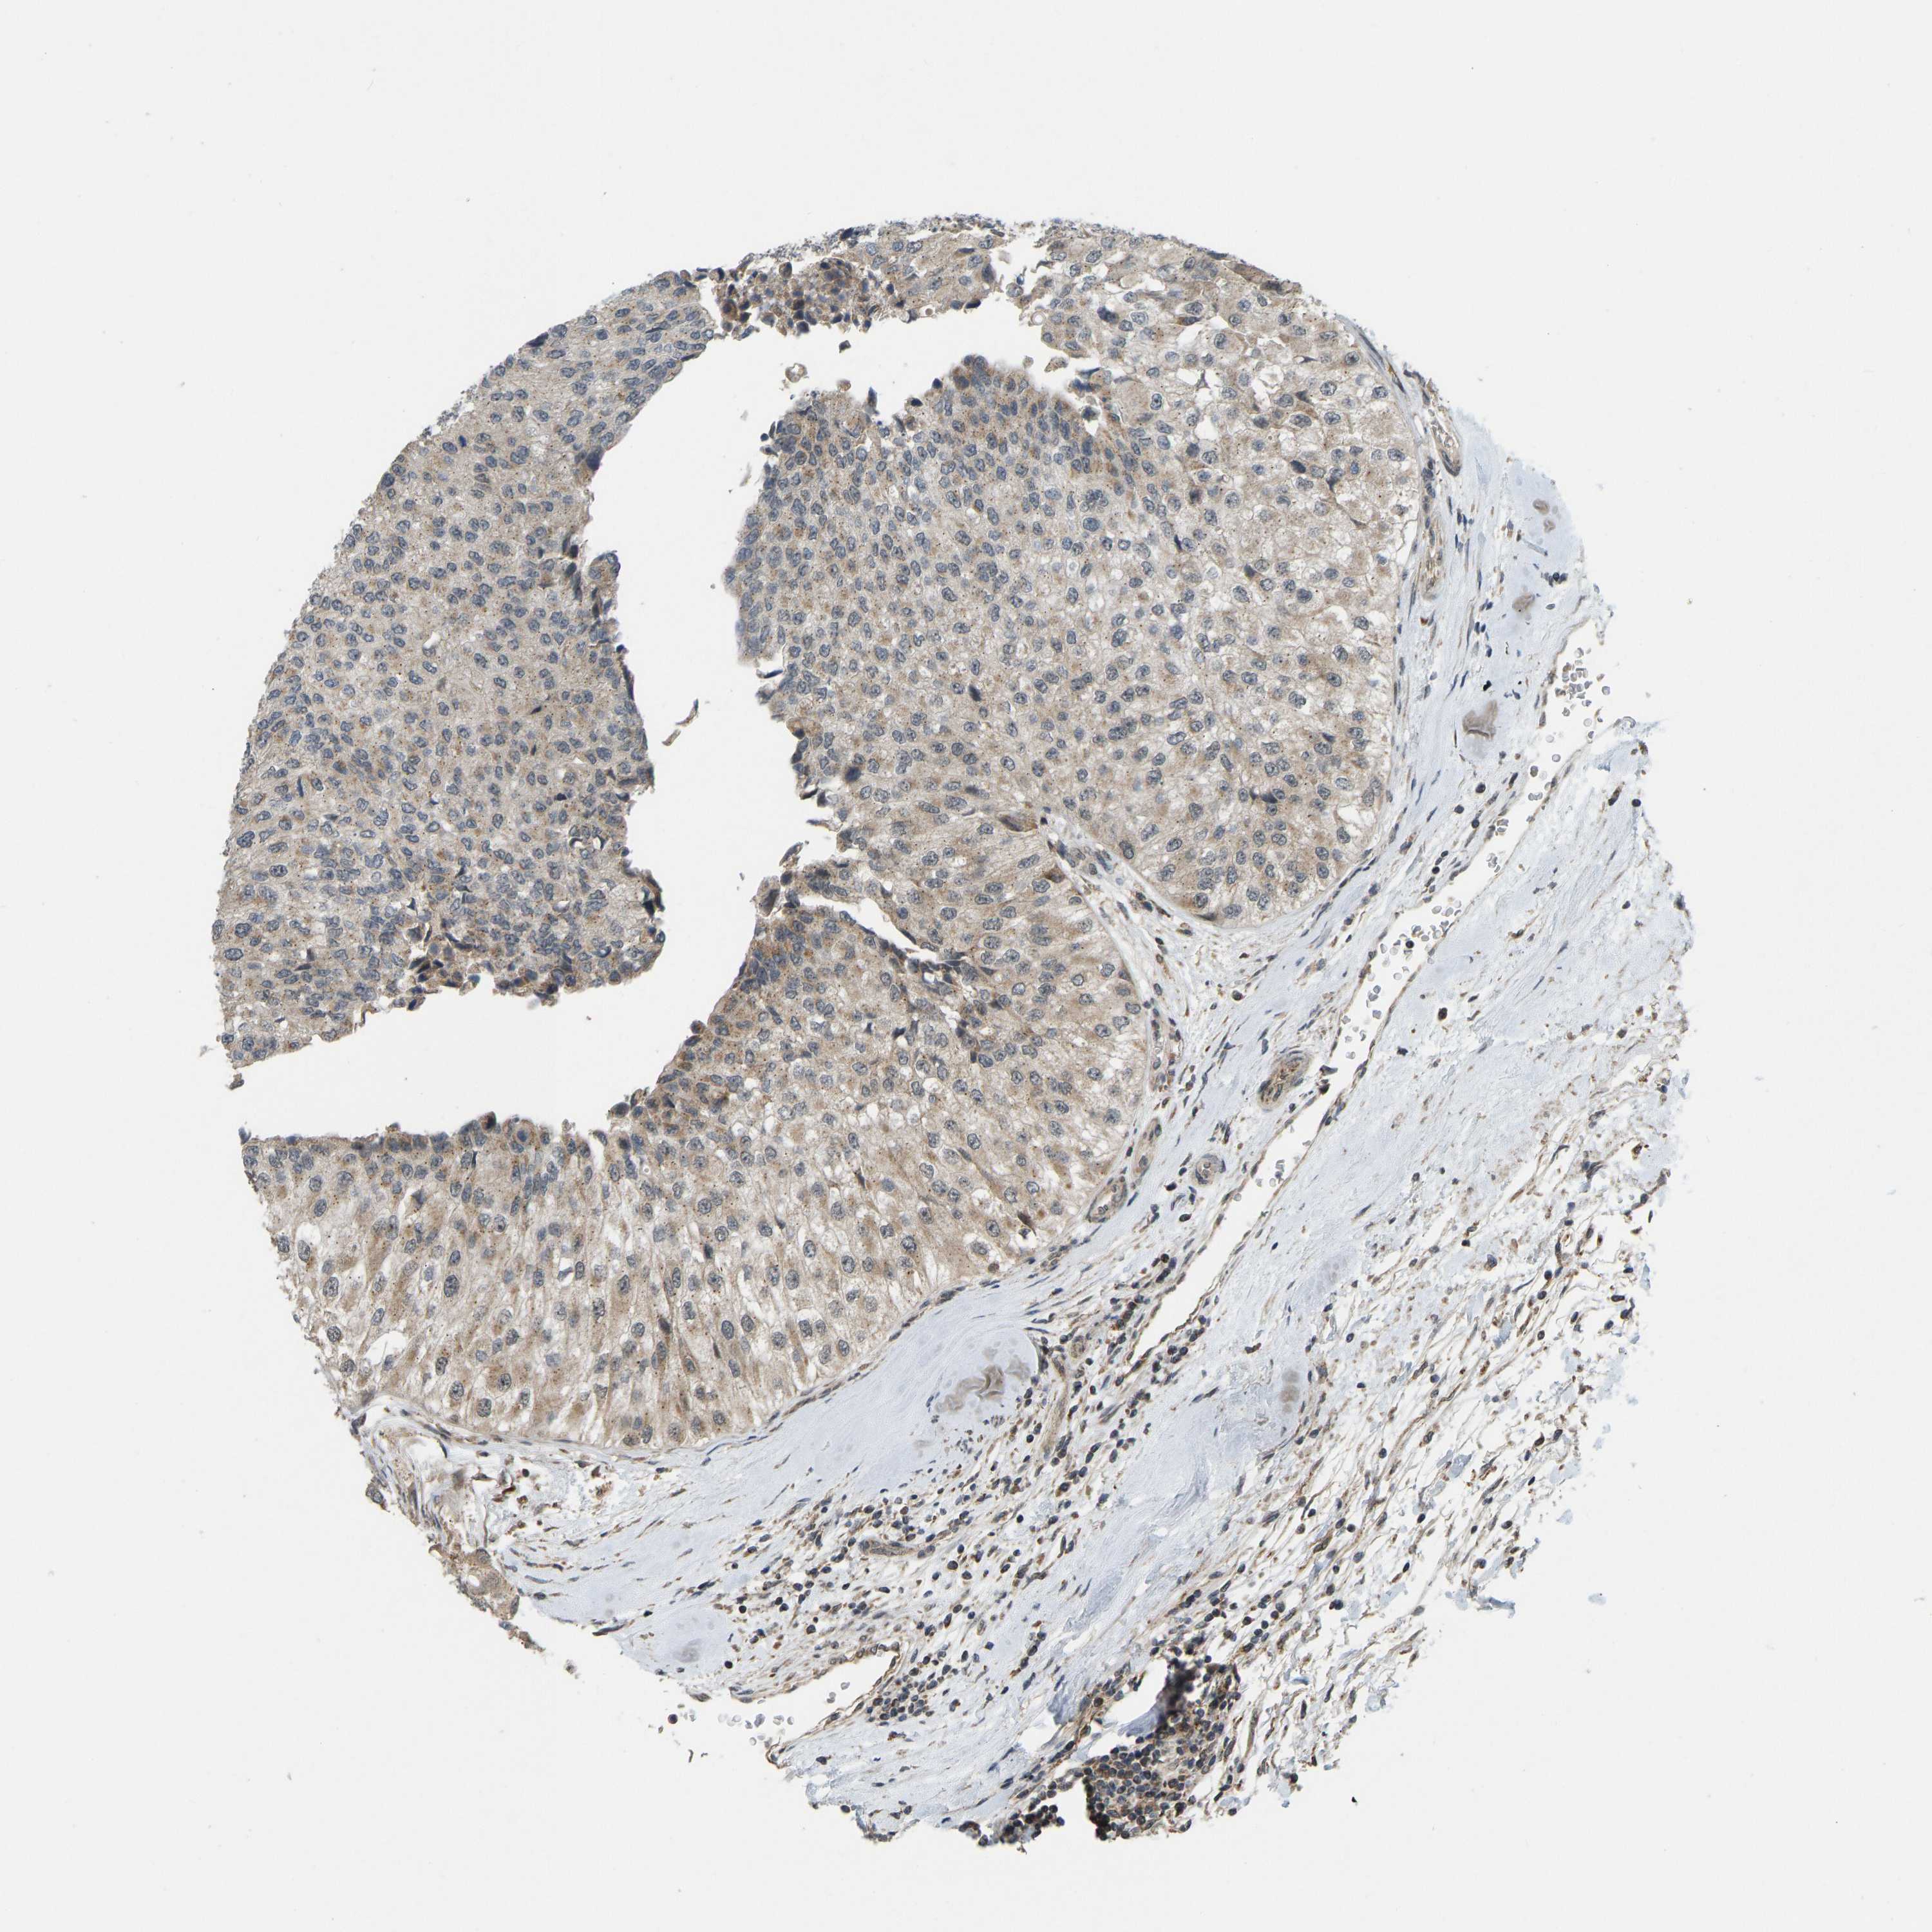

UROTHELIAL CANCER - Protein expressioni

A mouse-over function shows sample information and annotation data. Click on an image to view it in a full screen mode. Samples can be filtered based on level of antibody staining by selecting one or several of the following categories: high, medium, low and not detected. The assay and annotation is described here.

Antibody stainingi

Antibody staining in the annotated cell types in the current human tissue is reported as not detected, low, medium, or high, based on conventional immunohistochemistry profiling in selected tissues. This score is based on the combination of the staining intensity and fraction of stained cells.

Each image is clickable and will lead to virtual microscopy that enables deeper exploration of all samples and also displays staining intensity scores, fraction scores and subcellular localization as well as patient and tissue information for each sample.

Antibody HPA022271

Antibody CAB019284

Staining

High

Medium

Low

Not detected

Intensity

Strong

Moderate

Weak

Negative

Quantity

>75%

75%-25%

<25%

None

Location

Nuclear

Cytoplasmic/membranous

Cytoplasmic/membranous,nuclear

Urothelial carcinoma, Low grade

Urothelial carcinoma, High grade